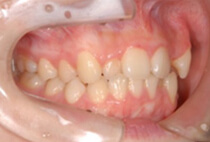

前歯のガタガタを気にして来院されました。なるべく抜かずに、短い治療期間で矯正治療を終わらせる治療をご希望されました。スピード矯正治療で、なるべく早期に前歯の審美性を改善することにしました。

コルチコトミー(スピード矯正処置)後1ヶ月の様子です。

上顎のみの舌側矯正治療ですが、下の歯には治療後半の噛み合わせを調節する段階で装置をセットしました。コルチコトミーを行ったことで、1ヶ月後には前歯のガタガタが大幅に改善できました。また、治療期間の短縮でけでなく、非抜歯できれいな歯並びに治療できました。